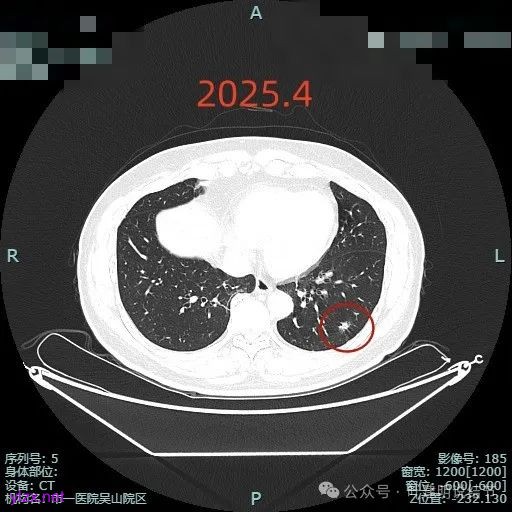

再看2025年4月初复查的情况:

整体纵向仍偏长条些,实性部分不太致密,边上磨玻璃成分的轮廓与界限不太清楚,毛刺显得长。

仍有支气管扩张,但较2024年时密度感觉低了点。

密度较淡且缺乏收缩力。

密度杂乱,血管进入,但血管说不上明显异常增粗,磨玻璃成分淡而瘤肺界限欠清。

总体较之前密度有减低,缺乏聚拢性。

我考虑较前好转,应该是慢性炎,建议9个月后再复查。